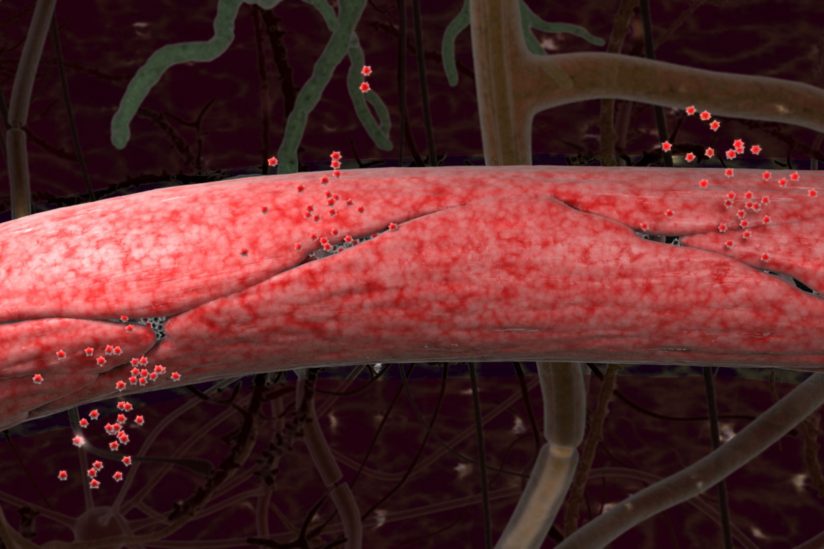

I farmaci antiipertensivi differiscono riguardo al rallentamento del declino cognitivo correlato all'età? Questo è oggetto di un ampio dibattito [rif. 1,2,3,4,5,6].I 'bloccanti del recettore II dell'angiotensina' (ARB, angiotensin receptor II blockers)...